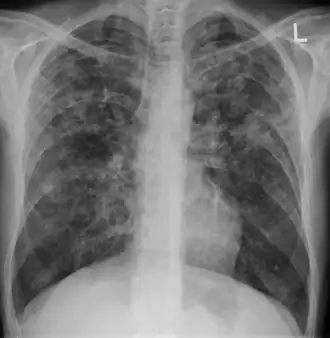

| Chest X ray showing miliary tuberculosis | |

Miliary tuberculosis is a form of tuberculosis that is characterized by a wide dissemination into the human body and by the tiny size of the lesions (1–5 mm). Its name comes from a distinctive pattern seen on a chest radiograph of many tiny spots distributed throughout the lung fields with the appearance similar to millet seeds—thus the term "miliary" tuberculosis. Miliary TB may infect any number of organs, including the lungs, liver, and spleen.[2]

Testing for miliary tuberculosis is conducted in a similar manner as for other forms of tuberculosis, although a number of tests must be conducted on a patient to confirm diagnosis.[3] Tests include chest x-ray, sputum culture, bronchoscopy, open lung biopsy, head CT/MRI, blood cultures, fundoscopy, and electrocardiography.[9] The tuberculosis (TB) blood test, also called an Interferon Gamma Release Assay or IGRA, is a way to diagnose latent TB. A variety of neurological complications have been noted in miliary tuberculosis patients—tuberculous meningitis and cerebral tuberculomas being the most frequent. However, a majority of patients improve following antituberculous treatment. Rarely lymphangitic spread of lung cancer could mimic miliary pattern of tuberculosis on regular chest X-ray. [14]

A case of miliary tuberculosis in an 82-year-old woman:

X-ray, 13 days after onset, showing bilateral interstitial infiltrates -

X-ray, 22 days after onset, showing extensive bilateral reticulo-nodular infiltrates -